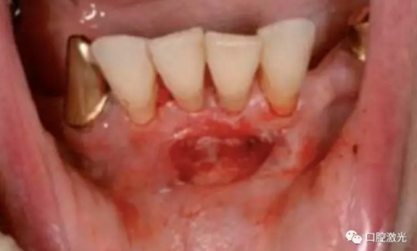

種植體暴露術(shù)術(shù)前

術(shù)中

愈合基臺安裝前

愈合基臺安裝后